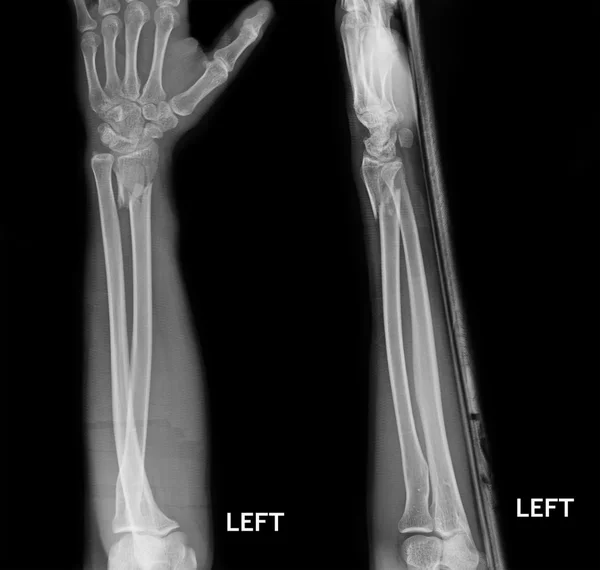

Midshaft Radius And Ulnar Fractures Image Radiopaedia vrogue.co Radius Ulna Fracture At Elbow planning & preparation. Identify fracture pattern, location, displacement, comminution,. patients with radius or ulna fractures often present with reduced range of motion in the joint adjacent to the fracture (i.e., wrist for distal fracture and elbow for proximal fracture). the two bones of the forearm (the radius and ulna) allow flexion and extension at the elbow and. Radius Ulna Fracture At Elbow.

Radius and Ulna shaft fractures — Radius Ulna Fracture At Elbow Identify fracture pattern, location, displacement, comminution,. patients with radius or ulna fractures often present with reduced range of motion in the joint adjacent to the fracture (i.e., wrist for distal fracture and elbow for proximal fracture). planning & preparation. if the elbow and wrist are not adequately visualised, ap and lateral views of these joints should be. Radius Ulna Fracture At Elbow.

Radius Ulna Fracture At Elbow . the two bones of the forearm (the radius and ulna) allow flexion and extension at the elbow and the wrist via diarthrodial joints. Identify fracture pattern, location, displacement, comminution,. radius and ulnar shaft fractures, also known as adult both bone forearm fractures, are common fractures of the forearm caused. Radial head fractures are common. planning & preparation. if the elbow and wrist are not adequately visualised, ap and lateral views of these joints should be obtained to eliminate. fractures of the radius often occur in the part of the bone near the elbow, called the radial head. patients with radius or ulna fractures often present with reduced range of motion in the joint adjacent to the fracture (i.e., wrist for distal fracture and elbow for proximal fracture).